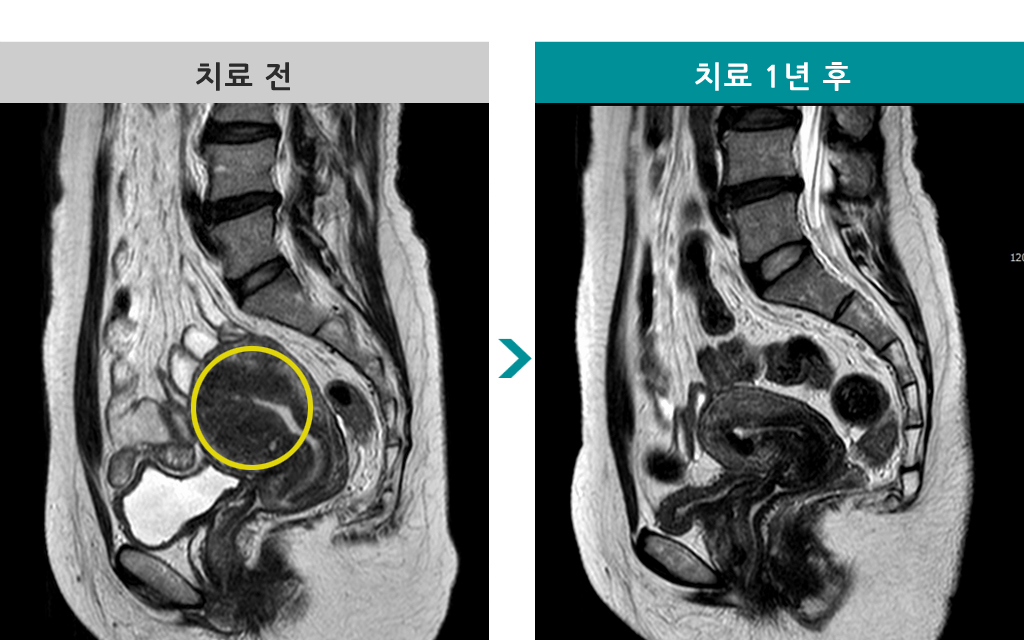

48세 [자궁근종 색전술] 전후 MRI사진 비교 - 86% 감소